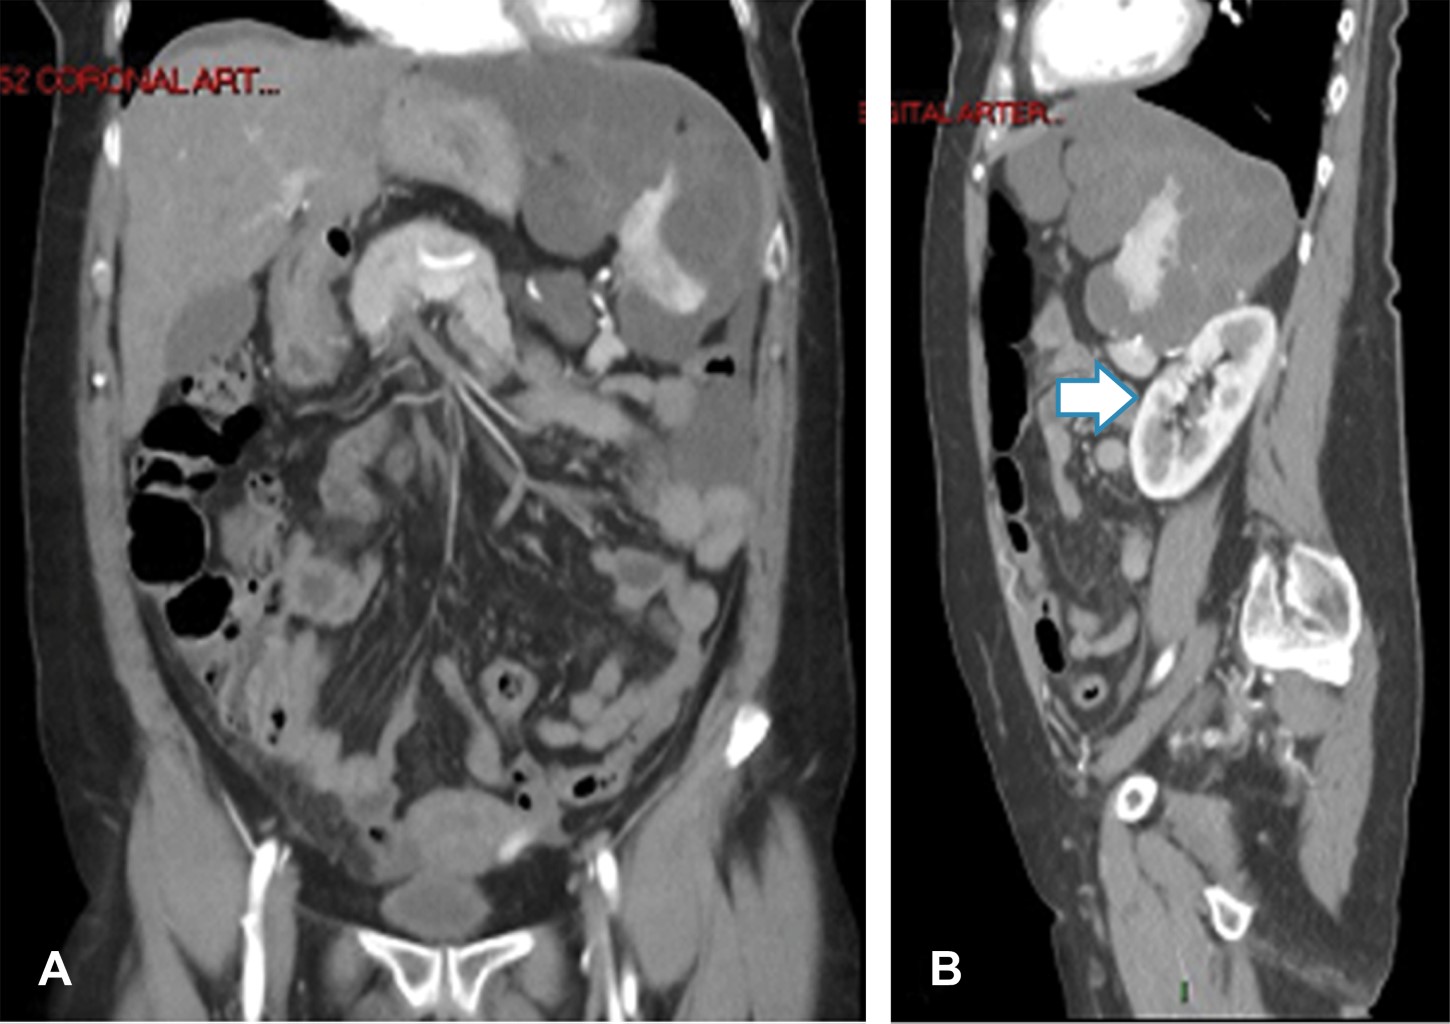

Se le solicitó una tomografía computarizada de abdomen en fase simple y contrastada; se encontró una lesión ovoidea, heterogénea a expensas de zonas hipodensas que alternaban con otras de mayor densidad, mostrando atenuación grasa dependiente del peritoneo que infiltraba y causaba festoneado del bazo, la lesión midió 29.1 × 14.2 × 27.3 cm (Figura 1). Tras la aplicación del medio de contraste se mostró reforzamiento heterogéneo con dilatación y tortuosidad de los vasos, esta masa causaba desplazamiento medial, caudal y ventral del riñón izquierdo, lateral y anterior del páncreas así como lateral del duodeno (Figura 2). Se realizó el diagnóstico de pseudomixoma peritoneal por tomografía. La paciente fue trasladada a un hospital de tercer nivel para su manejo.

Figura 1